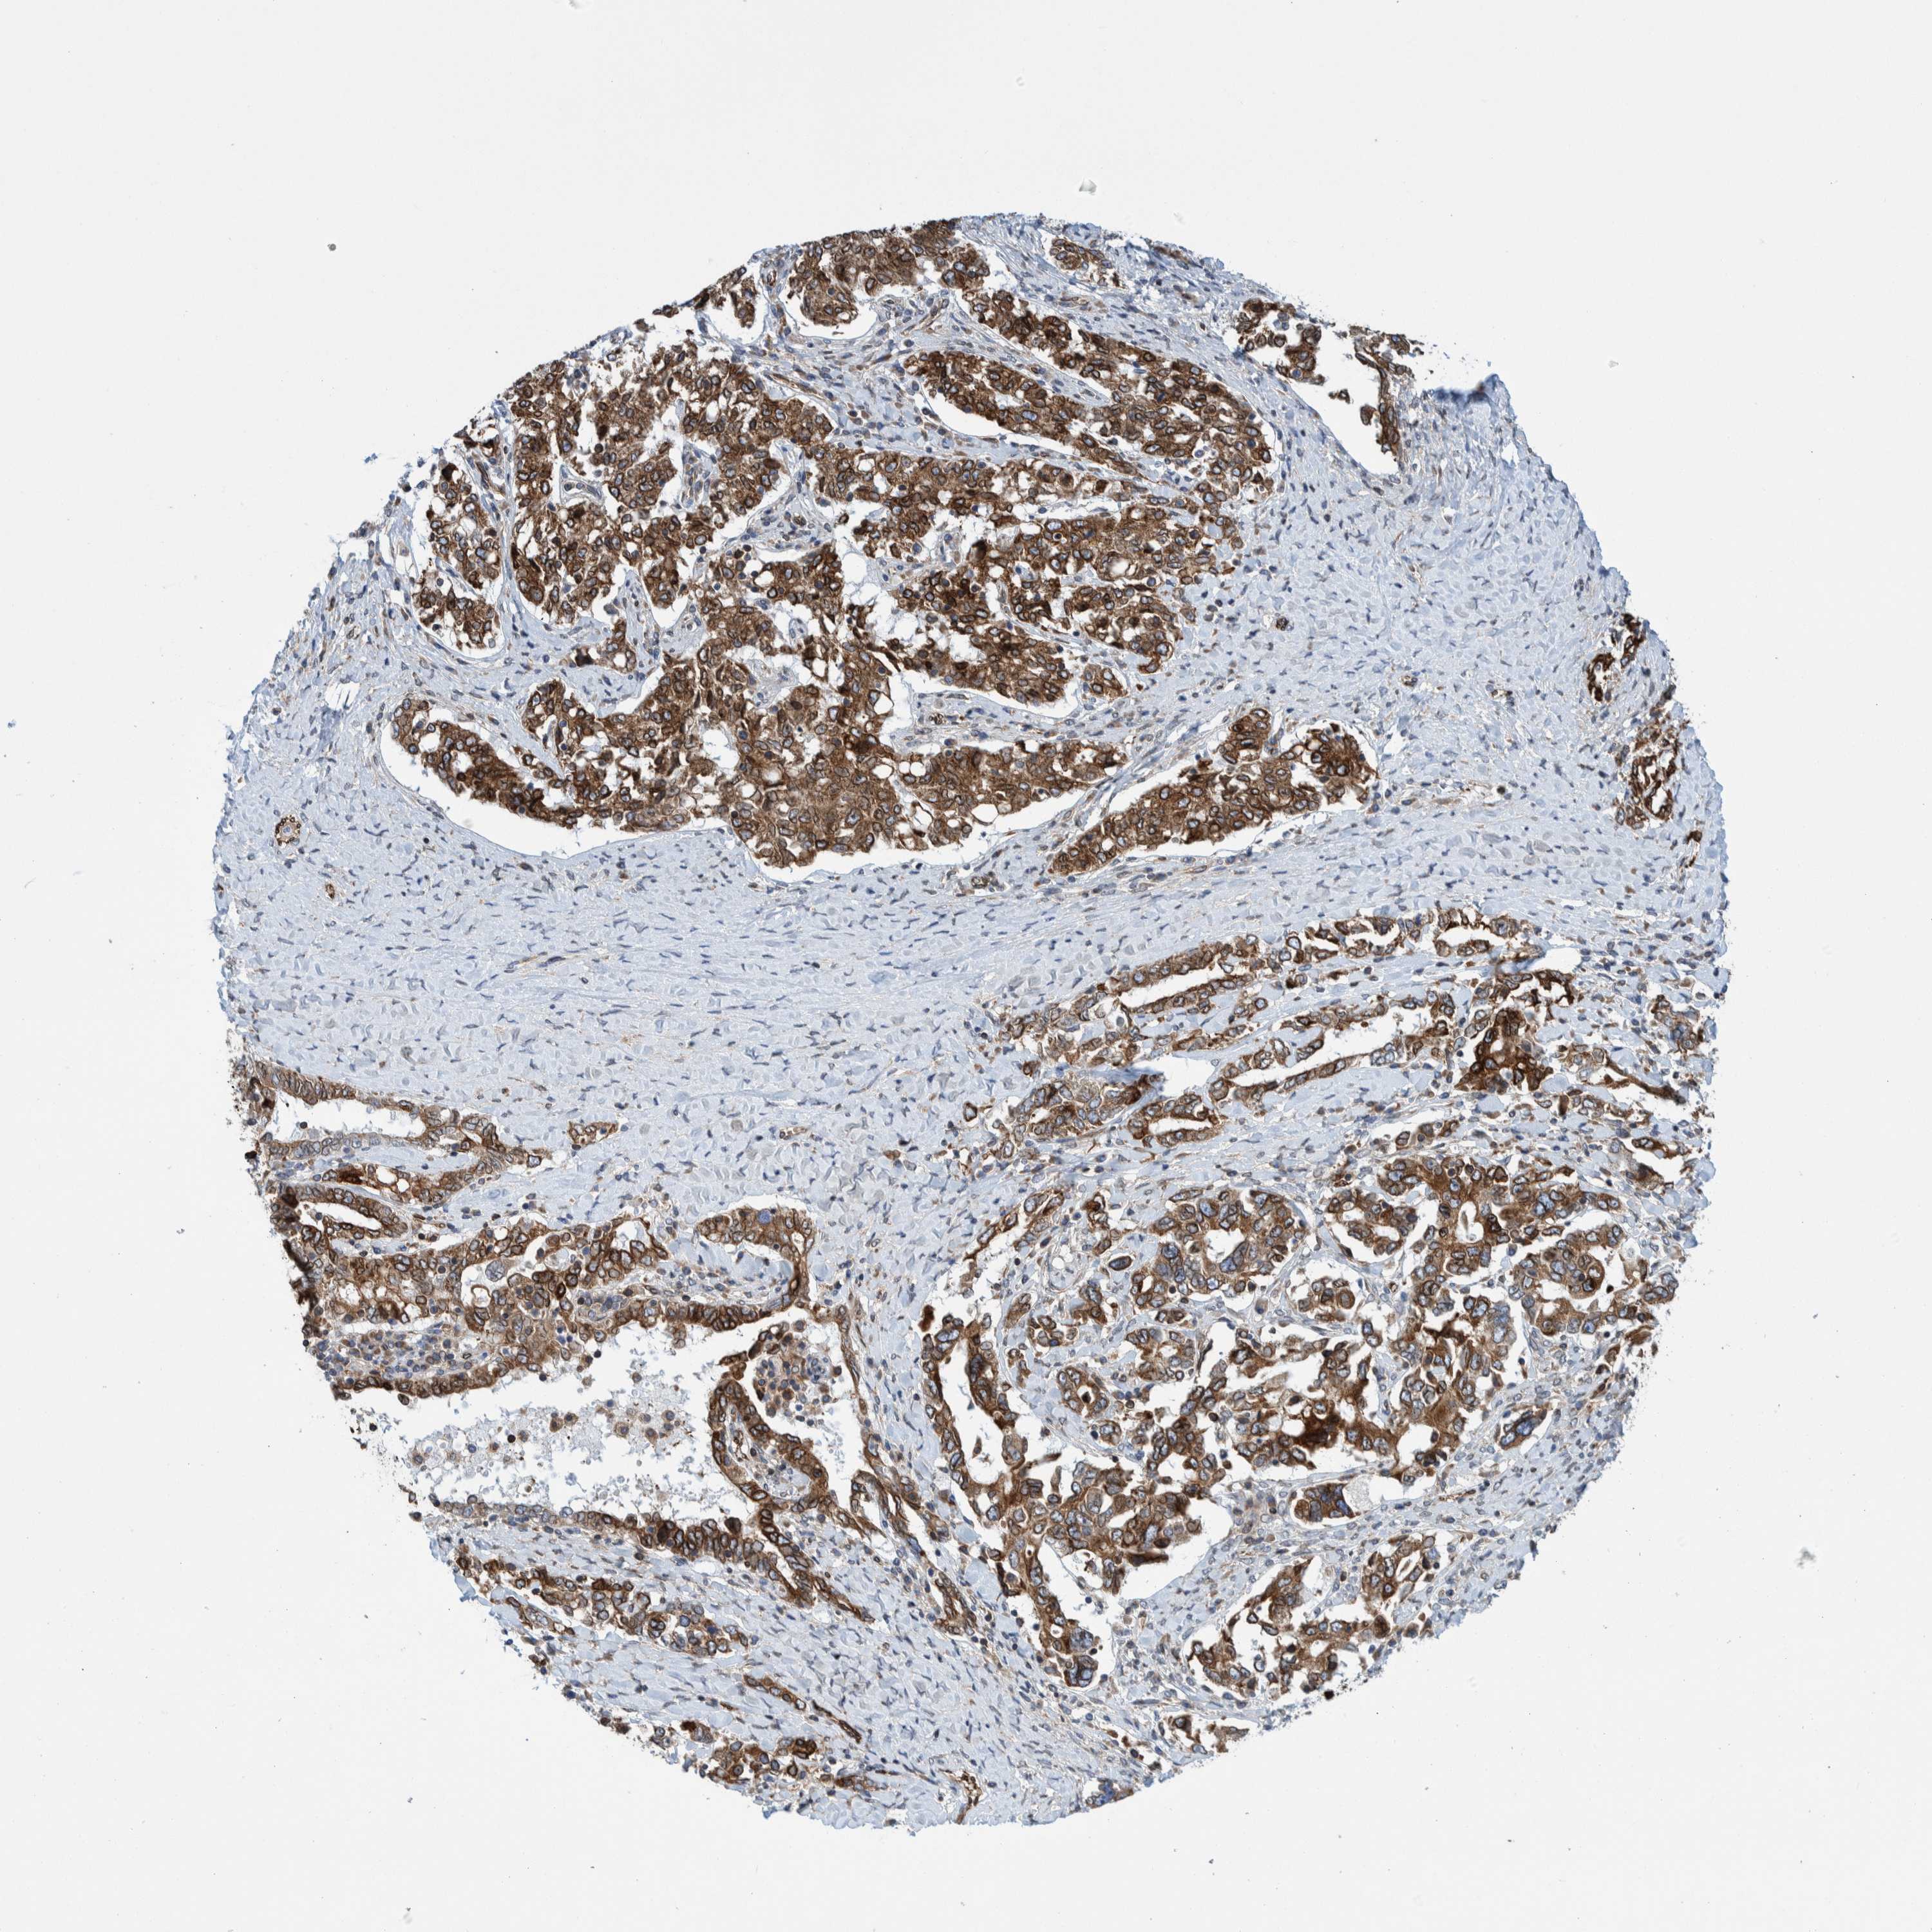

OVARIAN CANCER - Protein expressioni

A mouse-over function shows sample information and annotation data. Click on an image to view it in a full screen mode. Samples can be filtered based on level of antibody staining by selecting one or several of the following categories: high, medium, low and not detected. The assay and annotation is described here.

Note that samples used for immunohistochemistry by the Human Protein Atlas do not correspond to samples in the TCGA dataset.

Antibody stainingi

Antibody staining in the annotated cell types in the current human tissue is reported as not detected, low, medium, or high, based on conventional immunohistochemistry profiling in selected tissues. This score is based on the combination of the staining intensity and fraction of stained cells.

Each image is clickable and will lead to virtual microscopy that enables deeper exploration of all samples and also displays staining intensity scores, fraction scores and subcellular localization as well as patient and tissue information for each sample.

Antibody HPA023255

Staining

High

Medium

Low

Not detected

Intensity

Strong

Moderate

Weak

Negative

Quantity

>75%

75%-25%

<25%

None

Location

Nuclear

Cytoplasmic/membranous

Cytoplasmic/membranous,nuclear

Cystadenocarcinoma, serous, NOS

Carcinoma, endometroid

Cystadenocarcinoma, mucinous, NOS

Carcinoma, NOS